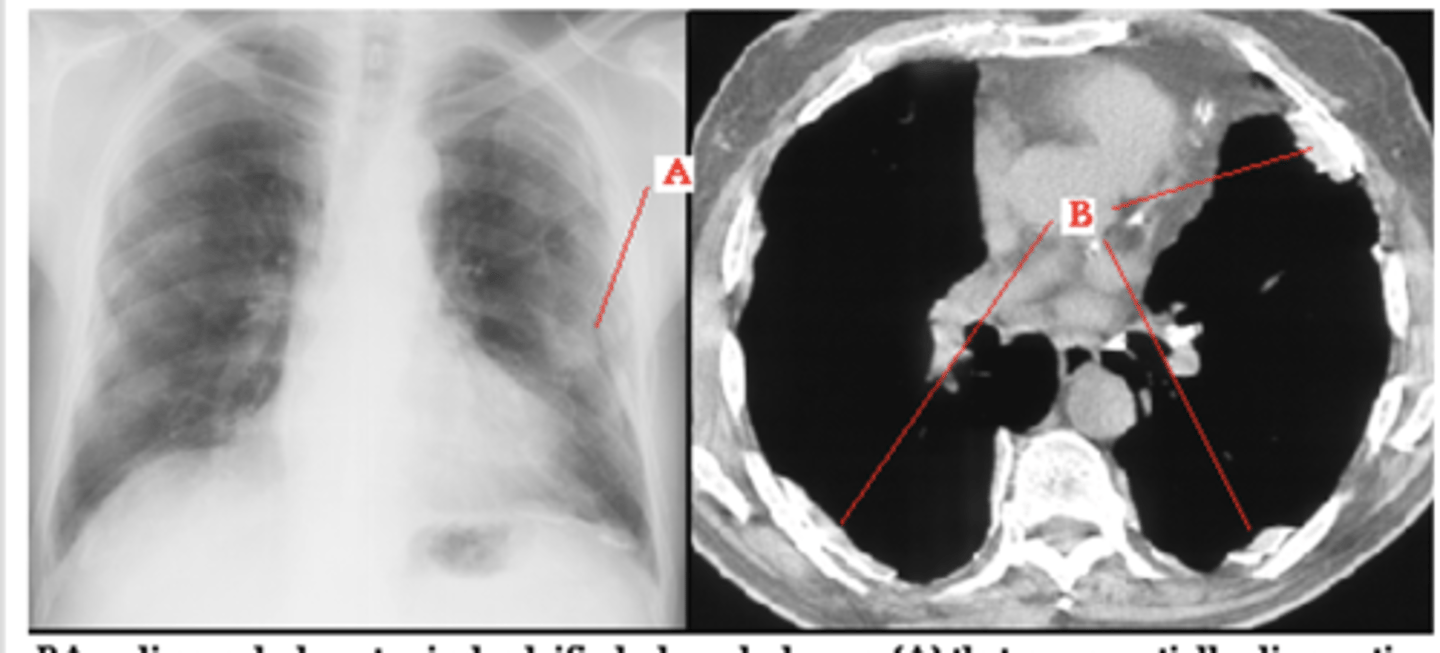

Left image: Thymoma in patient with Myasthenia Gravi

-Focal lesions are caused by masses

-Diffuse lesions are caused by infection, bleeding or infiltrating tumor

thymoma

-no need to interpret image

enlarged lymph nodes

Mass obscuring the right tracheal border - lymphadenopathy

middle

What compartment is this lesion in?

ganglionic lesion

-posterior compartment because neurogenic

-Posterior mediastinal masses can show a double density over left side of heart.